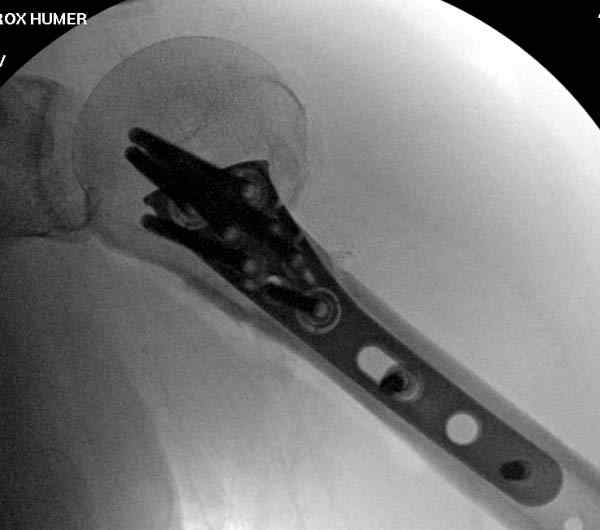

После устранения смещения пластина установлена выше (5,6,7) и финальные снимки (8,9,10)

Подбор импланта тоже имеет значение, например многие импланты направлены для фиксации перелома без учета ротаторной манжетки. Предпочтительными являются низко сидящие полиаксиальные пластины, где верхние шурупы можно проводить под углом в 120 градусов. (11)